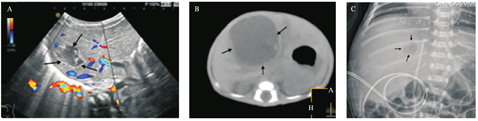

影像学检查:7例患儿的肝脏超声检查均提示肝内不规则混合声团(图1A),仅发生于左叶2例、右叶3例,两叶同时发生2例。胸腹部X线检查显示7例患儿的肝区均出现囊状透亮影(图1B)。5例患儿进行了上腹部CT检查,均提示肝内存在低密度病灶(图1C)。

A.超声:肝脏内混合回声包块,内见散在光带回声,囊性包块及周边内部及周边未见血流信号;B.X线:右腹肝区可见囊状透亮影;C.CT:肝内见一巨大低密度灶。